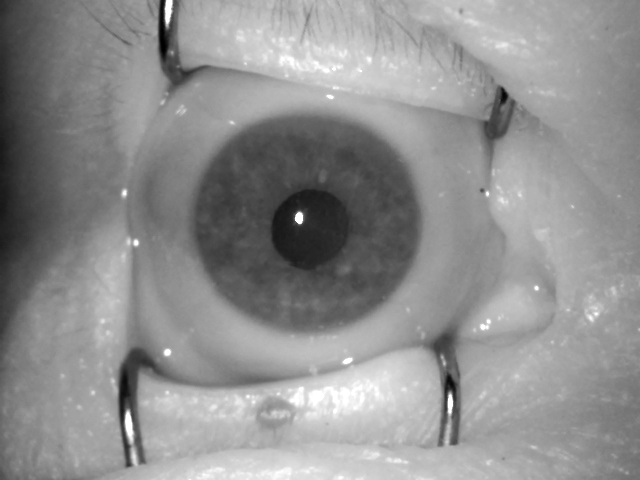

IV-A2 The cornea

The most prominent metamorphoses observed in the eyes after death, and possibly the most troubling for iris recognition, are the changes to the cornea. A live cornea is a clear, transparent, dome-shaped structure in front of the eyeball. It is responsible for about 2/3 of the total eye optical power because of its curvature and the resulting refractive index. The cornea must remain transparent to refract light properly, but also to allow good quality iris image capturing. Its transparency is maintained by a controlled hydration with the tear film, produced by lacrimal glands and distributed by eyelids. As secretion stops, anoxia, dehydration and acidosis lead to progressing autolysis of the cells. Corneal thickness decreases immediately after death and increases thereafter. This results in opacification that increases with time. Upon death the cornea slowly becomes hazy. The change in corneal opacity is believed to be secondary to the change in hydration and architectural destruction of the collagen fiber network, functional alteration of corneal endothelium, disregulation of proteoglycan hydration and ion concentration in corneal stroma. It was confirmed that temperature has significant influence on protein degradation. Another effect associated with these mechanisms is the wrinkling of the corneal surface, manifesting itself with difficulties to obtain a good visibility of the underlying iris pattern. The progression of these effects is influenced by multiple factors, such as closure of the eyelids, environment humidity, temperature, and air movement. It is also dependent on the age and general medical condition of a deceased person. Due to reduced intraocular pressure, we can also notice central depression of the globe, flaccidity of the eyeball, and loss in its firmness [17].

IV-A3 The iris

There are no evident changes to the iris surface observed after death. After demise, pupils are usually mid-dilated (a.k.a. ‘cadaveric position’), and in some cases they can be slightly dilated, because of the relaxation of the iris muscles and later they can become slightly constricted with the onset of rigor mortis of the constrictor muscles. In other cases, we may observe initial myosis within the first few hours after death with strong variations between individual cases. If rigor mortis affects ciliary muscles of two irises unequally, pupils in both eyes may have different apertures. Sometimes, if different segments of the same iris are unequally affected then the pupil may be irregularly oval or have an eccentric position. Shape and size of the pupils can also depend on the medical history of the subject, including treatment with drugs and eye surgeries.

IV-B Visual Inspection of Post-Mortem Changes

We have taken the effort to carefully examine the samples throughout the time period since death for all subjects, and confront the observed changes with medical knowledge. This yielded a qualitative evaluation of post-mortem changes to the iris reported in this Section. Having both NIR and VIS images is crucial for such assessment, as these two types of illumination often reveal different appearance of the iris when changes to the cornea and the anterior chamber are present. This is shown in Fig. 3, where visible-light samples are compared against near-infrared samples for the same eye. Such differences are also reported on in the works of Aslam et al. [20] and Trokielewicz et al. [21] related to the disease influence on iris recognition performance. Both studies show that the NIR illumination typically used in iris recognition cameras is capable of alleviating corneal opacification effects to some extent.

A summary of example post-mortem changes that appear in the eye is presented in Fig. 2, together with a timeframe for a selected subject. It must be noted, however, that the dynamics of these changes are heavily subject-dependent and can happen with different rapidity, intensity and prevalence on the appearance of iris tissue.

First, a corneal opacification progresses with time since death, and it becomes visible after a few days post-mortem (e.g., 95 hours, or 4 days, after death, as depicted in Fig. 2). Second, a wrinkling of the corneal surface is expected to appear (e.g., 359 hours, or 15 days, as shown in Fig. 2). At this point, a strong influence on the automatic image segmentation procedures can be anticipated, as the iris tissue becomes less visible and additional patterns and light reflections emerge. Third, a loss of intraocular pressure in the eyeball due to post-mortem biochemical changes can be observed (e.g., 574 hours, or 24 days, as illustrated Fig. 2), causing the eye to slowly collapse into the eye socket. At this point in time, iris recognition methods are expected to seldom work, as the iris pattern is severely obstructed and thus challenging for iris image segmentation. Finally, after about a month, the eyeball was observed to dry out completely, leaving no traces of a healthy iris structure.

Contrary to initial predictions, we did not come across any sample that would be affected by tache noire. Also, the severe corneal opacification was visible in original VIS samples only, while NIR and R images worked in favor of exposing post-mortem iris texture better than original VIS samples, as depicted in Fig. 3.